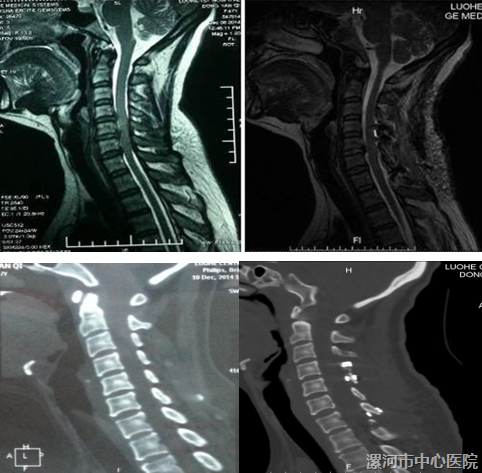

市创新性科研团队(脊柱科团队)设计了“保留颈2、3棘突肌肉止点的颈椎管成型术”。2008年以来,采用该创新型术式治疗 临床上较为多见的颈4~颈7狭窄的CSM。

只显露颈4~7的椎板,从而不切断附着在颈2、3棘突上的SSC,颈3椎板下半部潜行切除、胸1椎板上半部切除、颈4~7单开门

这样减压长度仍为5个节段(短了不利于脊髓后移),又较为完整的保留了 重要的SSC。

颈2、3棘突保留

应用超声骨刀行保留颈半棘肌止点的新式手术